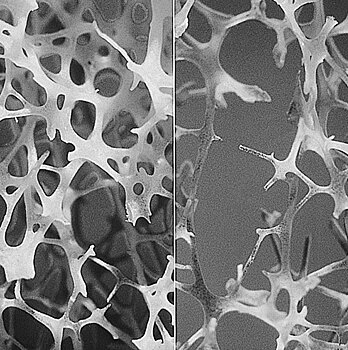

Обнаружена молекула, ответственная за развитие остеопороза

Первое в своем роде исследование, опубликованное в научном журнале Journal of Gerontology: Biological Sciences, показывает, что с возрастом уровни определенной молекулы увеличиваются, что приводит к уменьшению другой молекулы, которая создает здоровую кость. Исправление этого дисбаланса может улучшить здоровье костей и, возможно, покажет новые пути лечения остеопороза. Распространенность остеопороза Остеопороз поражает около 200 миллионов женщин во всем мире. Считается, что одна из трех женщин и 1 из 5 мужчин старше 50 лет имеют перелом костей в результате остеопороза. Новое исследование приближает нас к пониманию процесса, приводящего к разрушению костей при остеопорозе, и к потенциальным новым способам, которые могли бы решить проблему. Выводы объясняют ключевую молекулярную динамику, которая объясняет прогрессивную хрупкость наших костей по мере старения. Функция SDF-1 и microRNA-141-3p Садананд Фульзель (Sadanand Fulzele) объясняет процесс формирования костей, который начинается с мезенхимальных стволовых клеток. Эти стволовые клетки, которые могут развиваться как хрящ, кость или жир в костном мозгу. Одним из факторов, которые влияют на формирование этих клеток в конечном итоге, является сигнальная молекула, называемая фактор 1, выделенный из стромальных клеток (SDF-1). Предыдущие исследования показали, насколько важен SDF-1 для дифференциации мезенхимальных стволовых клеток в разные клетки, имеющие решающее значение для здоровья костей. SDF-1 важен для восстановления кости и защищает костные клетки от окислительного стресса, что является дисбалансом между свободными радикалами и антиоксидантами в организме и в конечном итоге приводит к повреждению ДНК и заболеванию. Кроме того, в предыдущих исследованиях было продемонстрировано снижение уровня SDF-1 у мышей старшего возраста; поэтому в этом исследовании ученые хотели точно понять, как регулируются уровни этой молекулы. В своих исследованиях доктор Фульзель показал, что небольшая молекула, называемая microRNA-141-3p, ингибирует витамин С, ключевой антиоксидант, таким образом предотвращая формирование наших костных клеток. Исследователи уже знали, что молекула может блокировать мезенхимальные стволовые клетки и не дает дифференцироваться в другие клетки, а также тот факт, что microRNA-141-3p увеличивается с возрастом. Поэтому ученые предположили, что microRNA-141-3p снижает SDF-1, и это один из основных способов, с помощью которых эта небольшая молекула прекращает формирование кости. Материалы и методы исследования Чтобы проверить эту гипотезу, Фульзель с соавторами проанализировали мезенхимальные клетки у людей и у мышей. Результаты научной работы Ученые обнаружили, что в молодых клетках уровни микроРНК-141-3p были низкими. Однако в старых клетках уровни этой молекулы утроились. Для уровней SDF-1 было обратное. Затем исследователи провели инъекцию microRNA-141-3p в мезенхимальные стволовые клетки, полученные от людей в возрасте 18-40 лет и от пожилых людей в возрасте 60-85 лет, которые прошли ортопедическую операцию. При инъеции microRNA-141-3p уровень SDF-1 резко падал и стволовые клетки становились жировыми. Кроме того, исследователи добавили microRNA-141-3p в костные клетки, что ухудшало функцию костной ткани. Однако применение ингибитора microRNA-141-3p улучшает функцию костной ткани. Выводы Результаты исследования показывают, что использование ингибитора microRNA-141-3p может помочь стволовым клеткам продолжать дифференцироваться в костные клетки, несмотря на возраст и состояние, такие как остеопороз. «Ингибитор нормализует функцию костей. Мы полагаем, что ингибитор может помочь нам сделать то же самое у людей», — утверждает Фульзель. «Если вам 20 лет, у вас отличная кость, у вас еще будет микроРНК-141-3p в ваших мезенхимальных стволовых клетках. Но когда вам 81, кость становится слабой». Исследователи планируют перенести свои результаты в доклинические модели, где хотят найти способы восстановления здоровых уровней микроРНК-141-3p и SDF-1. «Микро РНК -141-3p увеличивает экспрессию благодаря таким факторам, как старение, окислительный стресс и подавление эстрогена. Мы хотим вернуть его обратно в диапазон, который позволил бы эффективно влиять на нормальное образование костей», — говорит доктор Уильям Д. Хилл (William D. Hill). «Мы определили ряд микроРНК, которые меняются в стволовых клетках костного мозга со старением, и мы хотим понять, как они работают». Авторы другого исследования утверждают, что средиземноморская диета может замедлить потерю костной массы.